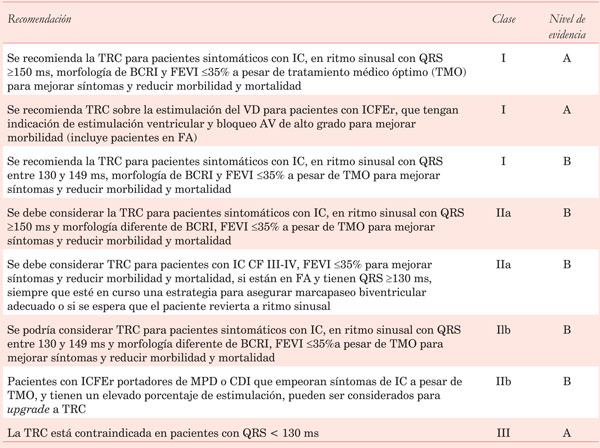

Tanto las guías europeas de ESC/EHRA13 como las estadounidenses de ACC/AHA/HRS29 tienen como indicación clase I la TRC-D en pacientes con IC CF II-III y IV ambulatoria, FEVI <35%, ritmo sinusal y BCRI con duración del QRS ³130 ms. Esta y otras recomendaciones de TRC se detallan en la (Tabla 3).

Tabla 3:Recomendaciones para el implante de resincronizador en pacientes con insuficiencia cardíaca (Guía europea de Insuficiencia cardíaca, 2016)28.